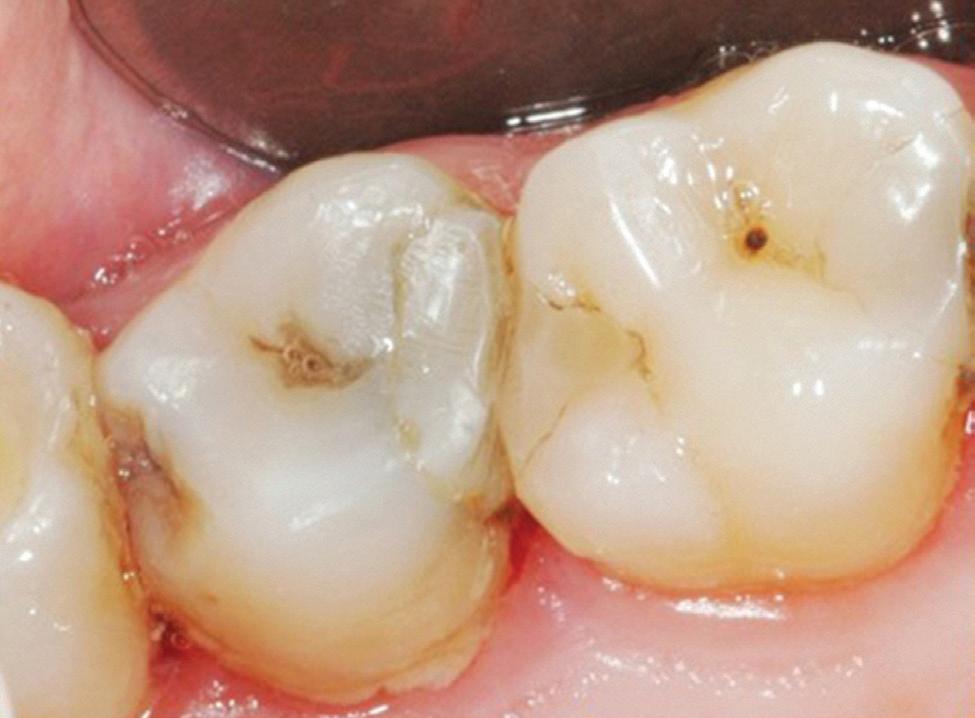

Estelite Asteria (Tokuyama)One of my favourite composite resin materials is Asteria which is a light-cured radiopaque composite for universal use. It considerably simplifies multilayer techniques yet delivers outstanding aesthetics with excellent polishability. Unlike mul tilayer techniques used with conventional composites, Asteria uses only 2 layers for optimal results without compromising aesthetics. The microstructure of the material produces a light diffusion that helps blend in with the natural tooth structure. The chameleon like nature of the material allows a blending of the materials to natural tooth structure and it allows excellent polishability which retains its lustre over time.